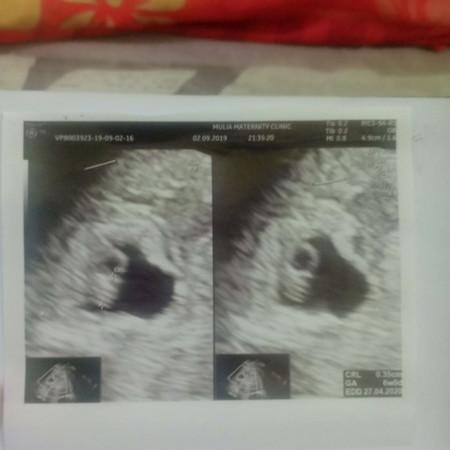

Ass... Bunda mohon do'anya aku lagi hamil usia 7w4d tapi pikiran ku lagi kalut banget bisa dibilang stress karena anak ke 2 ku meninggal bulan juli kemaren.... Aku tau ibu hamil gak boleh stress... Tapi aku gak bisa ngendaliin pikiran dan emosi ku... YaAlloh mohon do'anya bunda2 disini untuk ketenangan hatiku... Mudah2an janin ku berkembang dengan baik... Kemarin udah usg alhamdulillah udah tampak janin sama djj nya... Mudah2an selalu sehat dan berkembang dengan baik....